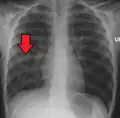

| Chest X-ray of a pneumonia caused by influenza and Haemophilus influenzae, with patchy consolidations, mainly in the right upper lobe (arrow) | |

Right middle lobe pneumonia in a child as seen on plain X-ray